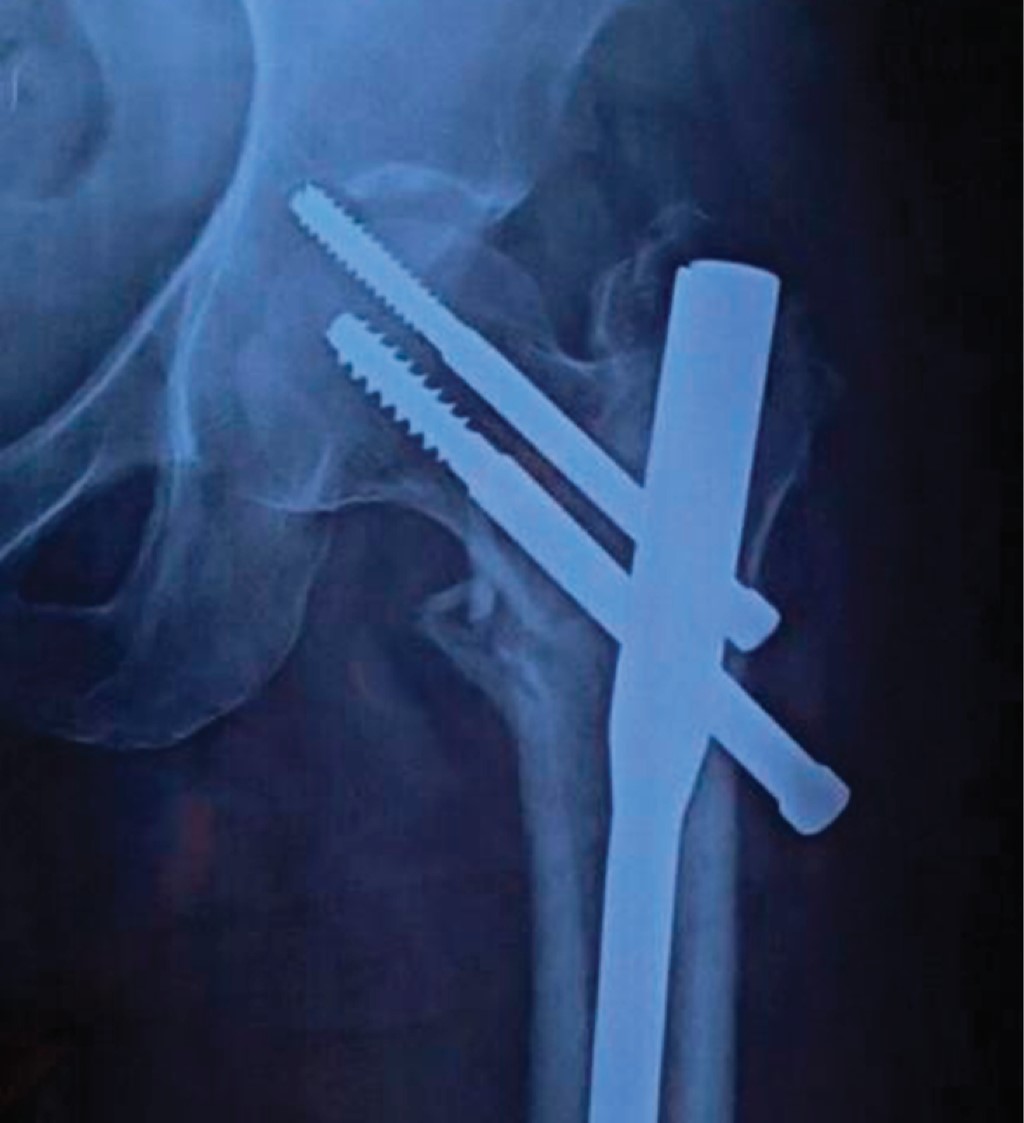

Implant related complications like screw back out (Figure 1), guide wire breakage (Figures 2 and 3), Z effect (Figure 4), TAD outliers (Figure 5) were more in PFN group whereas lateral screw protrusion, locking mechanism failure and barrel disengagement was more in PFNA2 group as shown in Figures 6, 7, 8 and 9. Neck shaft valgus outliers are more common in PFN group (Figure 10).

Implant-related complications, such as screw back-out, guidewire breakage, and proximal protrusion, were more pronounced in the PFN group, whereas lateral screw protrusion and medial migration were notable in the PFNA2 group.24 Lateral screw protrusion was observed in four patients in the PFNA2 group and one patient in the PFN group at the final follow-up in our study. Hu et al suggested a morphological mismatch in the Asian population between the proximal fragment of PFNA2 and the greater trochanter, leading to post-operative lateral trochanter pain.24